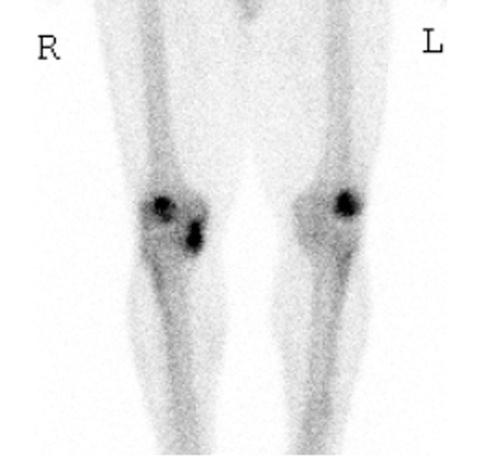

Although disorders of the patellofemoral joint are common in the athlete, their management can be challenging and require a thorough physical examination and radiologic evaluation, including advanced magnetic resonance imaging techniques.

Physical examination and imaging evaluation including standard radiographs are crucial in identifying evidence of malalignment or instability. Magnetic resonance imaging provides valuable information about concomitant soft tissue injuries to the medial stabilizers as well as injuries to the articular cartilage, including chondral shears and osteochondral fractures. Quantitative magnetic resonance imaging assessing the ultrastructure of cartilage has shown high correlation with histology and may be useful for timing surgery.

Evaluation of patellofemoral disorders is complex and requires a comprehensive assessment. Recent advancements in imaging have made possible a more precise evaluation of the individual anatomy of the patient, addressing issues of malalignment, instability, and underlying cartilage damage.